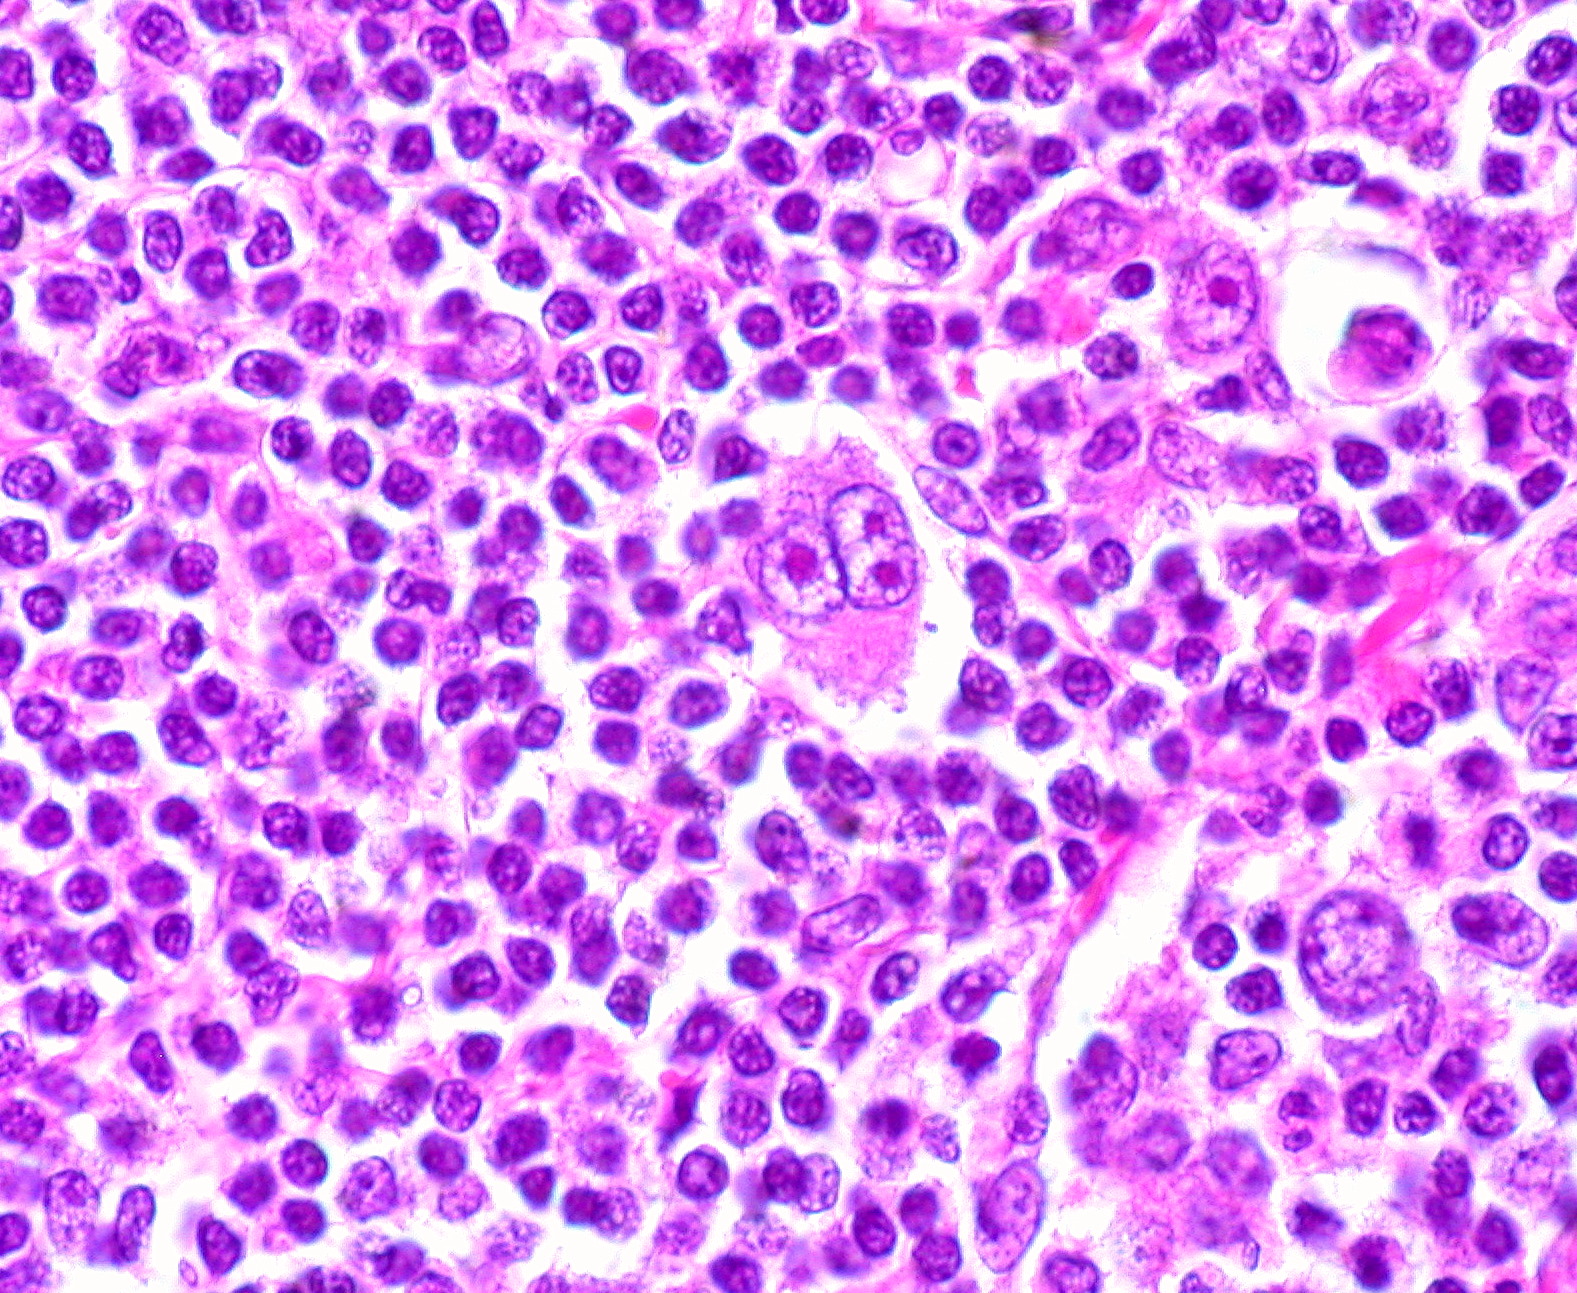

Микропрепараты: Лимфогранулематоз и Нодулярный Склероз

Раздел: Секреты мастерства